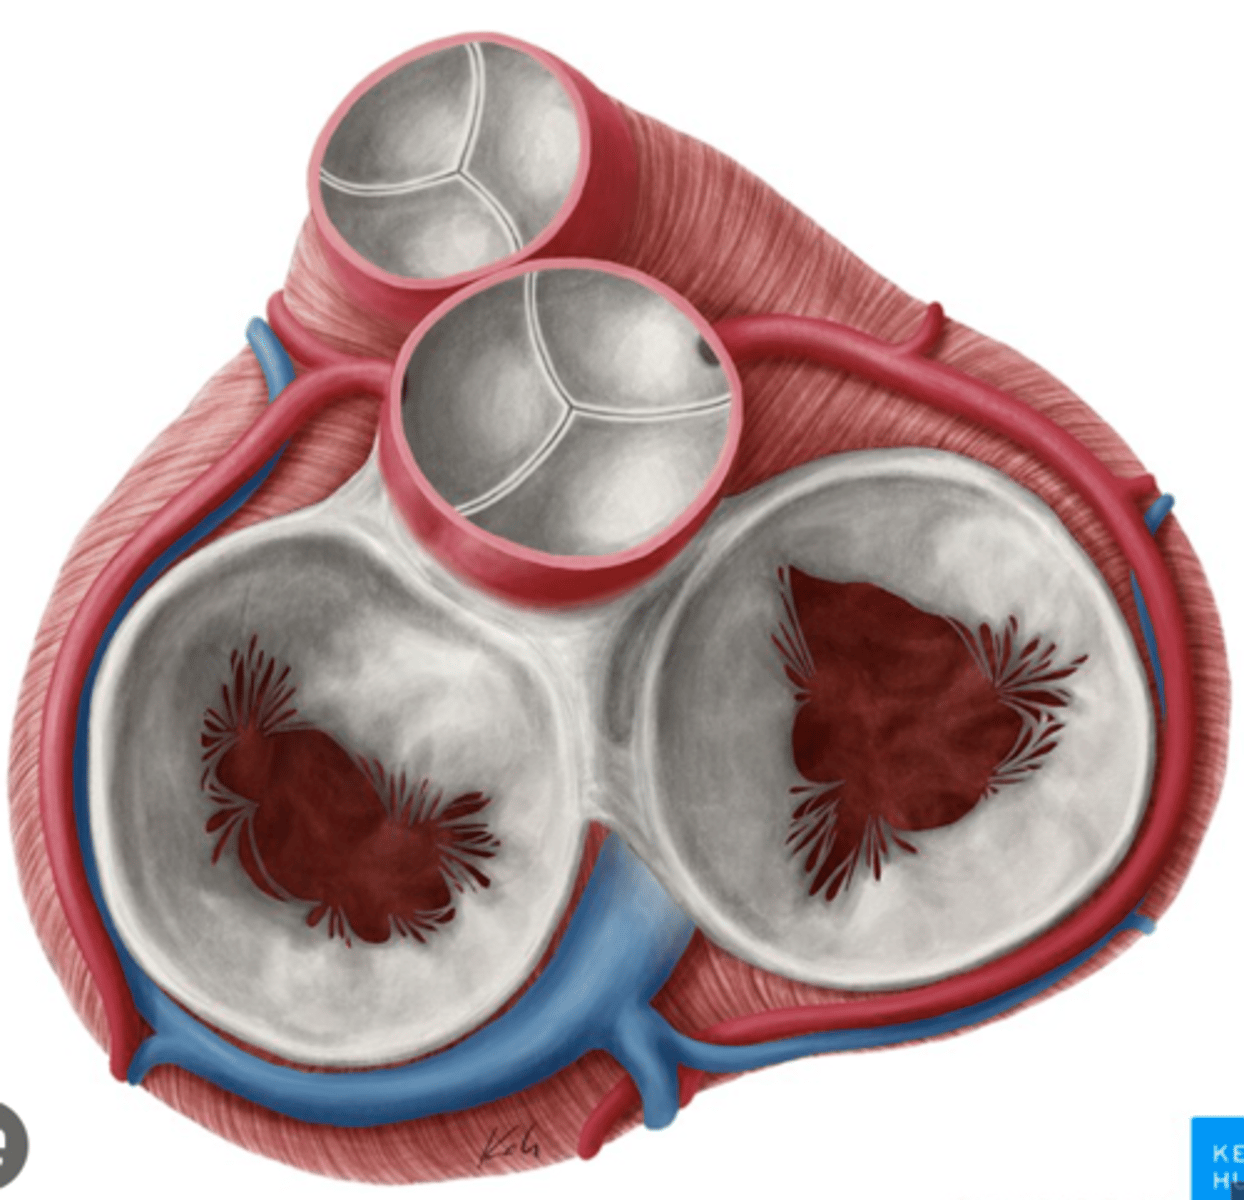

What are the valves separating atrium and ventricle?

. Tricuspid valve (right atrioventricular valve, 3 cusps)

. Mitral or bicuspid valve (left atrioventricular valve, 2 cusps)

What are the four valves in the heart?

Tricuspid

Mitral or bicuspid

Pulmonary

Aortic

What are other functions of the rings in the cardiac skeleton?

maintain the shape of the openings between the heart's chambers

insertion site for the cusps of the valves and muscular heart tissue.

What are the components of the cardiac skeleton?

. pulmonary ring,

. aortic ring

. AV rings

RINGS ARE IN THE SAME PLANE AROUND THE VALVES